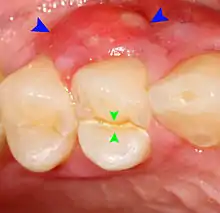

Clinical & xray correlation of pericoronitis

clinical shot of pericoronitis

An operculum (green arrow) over a partially erupted lower left third molar tooth. There is minimal inflammation and recurrent swelling.

xray of pericoronitis

A radiograph of the above tooth showing chronic pericoronitis, operculum (blue arrow) and bone destruction (red arrow) from chronic inflammation. Tooth is slightly disto-angular.

Pericoronitis is inflammation of the soft tissues surrounding the crown of a partially erupted tooth.[25] The lower wisdom tooth is the last tooth to erupt into the mouth, and is, therefore, more frequently impacted, or stuck, against the other teeth. This leaves the tooth partially erupted into the mouth, and there frequently is a flap of gum (an operculum), overlying the tooth. Bacteria and food debris accumulate beneath the operculum, which is an area that is difficult to keep clean because it is hidden and far back in the mouth. The opposing upper wisdom tooth also tends to have sharp cusps and over-erupt because it has no opposing tooth to bite into, and instead traumatizes the operculum further. Periodontitis and dental caries may develop on either the third or second molars, and chronic inflammation develops in the soft tissues. Chronic pericoronitis may not cause any pain, but an acute pericoronitis episode is often associated with pericoronal abscess formation. Typical signs and symptoms of a pericoronal abscess include severe, throbbing pain, which may radiate to adjacent areas in the head and neck,[21][26]:122 redness, swelling and tenderness of the gum over the tooth.[27]:220–222 There may be trismus (difficulty opening the mouth),[27]:220–222 facial swelling, and rubor (flushing) of the cheek that overlies the angle of the jaw.[21][26]:122 Persons typically develop pericoronitis in their late teens and early 20s,[28]:6 as this is the age that the wisdom teeth are erupting. Treatment for acute conditions includes cleaning the area under the operculum with an antiseptic solution, painkillers, and antibiotics if indicated. After the acute episode has been controlled, the definitive treatment is usually by tooth extraction or, less commonly, the soft tissue is removed (operculectomy). If the tooth is kept, good oral hygiene is required to keep the area free of debris to prevent recurrence of the infection.[21]:440–441